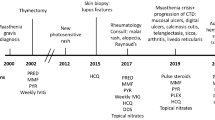

A 65-year-old African-American never-smoker vegan male with a past medical history of recurrent, transfusion-dependent anemia of unknown etiology of four years duration presented to an outside hospital with the chief complaint of abdominal pain. The review of the workup for his transfusion-dependent anemia revealed a severe normocytic, non-hemolytic anemia with iron studies indicative of anemia of chronic disease. Folate, cyanocobalamin, and thyroid stimulating hormone levels were normal (Table 1). Marrow biopsy failed to demonstrate any evidence of aplastic anemia or myelofibrosis, and the patient was given a presumptive diagnosis of PRCA, although no specific myeloid to erythroid ratio was available. On presentation to the outside facility, he was incidentally found to have a large mediastinal mass on chest X-ray (Fig. 1a), which was confirmed by computed tomography (CT) scan. CT imaging revealed a 11.7 × 9.8 × 7.6 cm right-sided, anterior mediastinal well-circumscribed mass without evidence of gross infiltration or necrotic, cystic, or calcified components, though it did deform the pericardium from extrinsic compression (Fig. 1b, c). Pathology from a CT-guided biopsy revealed thymoma. The patient was evaluated by cardiothoracic surgery who deemed the mass unresectable given its large size and tortuous anatomy, advising neoadjuvant chemotherapy for interim management. Anti-nuclear and acetylcholine receptor antibodies were negative at the time.

In consultation with oncology, a chemotherapeutic regimen of cisplatin, cyclophosphamide, and adriamycin commenced. In the months following initiation of chemotherapy, the patient’s red blood cell transfusion requirements decreased and an interval CT scan demonstrated a gradual reduction in the size of his thymoma to 9 × 5.5 × 11.5 cm. At that time, cardiothoracic surgery re-evaluated the patient and subsequently performed a complete thymectomy and thymomectomy. Gross and microscopic histopathology revealed benign thymus tissue with WHO class AB and modified Masaoka stage I thymoma, indicative of a well-circumscribed, grossly and microscopically encapsulated, noninvasive mass with characteristic lymphocyte-rich and lymphocyte-poor areas (Fig. 2a–d).

Despite initial improvement in his hemoglobin and transfusion requirements (transfusion threshold increased to Hgb of 6) following chemotherapy and thymectomy, the patient nevertheless remained severely anemic with a continued normocytic, non-hemolytic anemia, dependent on weekly red blood cell transfusions. He received a total of 150 red blood cell transfusions during a period of almost 40 months; however, there was no evidence of alloimmunization. Given his persistent anemia, he underwent repeat bone marrow biopsy 6 months post-thymectomy, which subsequently revealed a hypocellular marrow (20–30%) with difficult to identify erythroid precursors and a myeloid-erythroid ratio of greater than 10:1, indicative of erythroid hypoplasia. Megakaryocytes were normal in number and morphology, and occasional paratrabecular aggregates of small, mature lymphocytes were observed (Fig. 3a, b). Flow cytometry was negative for lymphoma, revealing no loss or aberrant expression of T lymphocyte cell antigens, a normal CD4/CD8 ratio, no evidence of monotypic population of B lymphocytes, and no increased blasts. He was referred for evaluation of bone marrow transplant, however declined further workup.

His transfusion dependency was subsequently complicated by iron overload, diagnosed in the setting of iron saturation of 93% and ferritin elevation up to 6000 ng/ml, for which deferasirox was initiated. He eventually acquiesced to a bone marrow transplant workup. Repeat marrow continued to demonstrate a hypocellular marrow with scant erythroid precursors and an elevated myeloid-erythroid ratio with normal myeloid lineage maturation, while flow cytometry continued to demonstrate no abnormalities. Whole-body positron emission tomography scan was negative for FDG-avid masses, suggesting no evidence of residual thymoma tissue or metastatic disease. An anti-nuclear antibody (ANA) was positive with a titer of 1:160 with speckled and homogenous patterns, which prompted further autoimmune workup and referral to rheumatology.

At the time of referral to rheumatology, ANA titer remained elevated (1:320) with a predominantly homogenous pattern. Anti-Smith and double-stranded DNA (ds-DNA) antibodies (Ab) were positive, whereas anti-histone Ab, ribonucleic protein (RNP) Ab, RNA polymerase 3 IgG Ab, Ro/SSA and La/SSB Ab, Scleroderma (SCL) 70 Ab, rheumatoid factor (RF), anti-neutrophil cytoplasmic antibody (ANCA), anticardiolipin Ab, thyroid antibodies, and beta-2 glycoproteins antibodies were negative. C3 and C4 complement levels were within normal limits (Table 1). Urine studies showed increased urine protein-creatinine ratio of 663 mg/g. He fulfilled not only the SLICC criteria, but also the EULAR criteria for diagnosis of systemic lupus erythematous (Table 2). It was recommended that he be started on hydroxychloroquine 400 mg daily; however, the patient declined as he did not agree with the diagnosis of lupus and the potential side effects of the proposed medication, despite ongoing discussion with the primary team as well as sub-specialty services. Hematology recommended immunosuppressive therapy, prednisone, and cyclophosphamide, to which he agreed. A comprehensive infectious workup prior to initiation of immunosuppression was unremarkable, and he was started on prednisone for 1 month to be followed by cyclophosphamide. In the setting of his aforementioned oral ulcers and oral dysphagia, however, he was unable to tolerate cyclophosphamide and further declined to pursue that option again. Other therapeutic options including methotrexate and cyclosporine were declined in the setting of adverse side effect profiles, and the patient decided to remain on intermittent palliative transfusions.

As his disease course continued, he gradually developed worsening thrombocytopenia (nadir of 5) and leukopenia, which was complicated by multiple hospitalizations in the setting of opportunistic infections with multi-drug resistant organisms such as extended spectrum beta-lactamase (ESBL) pneumonias and bacteremia. Multiple screening for other underlying causes of immunosuppression such as human immunodeficiency virus (HIV) infection were negative. Bone marrow biopsy and flow cytometry persistently failed to reveal any abnormality in platelet or lymphocyte precursors, with persistent erythroid hypoplasia. Unfortunately, the patient continued to decline immunosuppressive therapy, leading to an insidious decline in his clinical status, ultimately resulting in his death secondary to multi-drug resistant infections with ESBL organisms in the setting of pancytopenia.

The exact mechanism and pathogenesis of autoimmunity and paraneoplastic disease after thymectomy, its prevalence, and predisposition in certain patients remains to be elucidated. Bernard et al. concluded that no clinical nor pathological features predicted the development of autoimmune disorders post-thymectomy and that preexisting autoimmunity was not identified as a risk factor for autoimmunity post-thymectomy [1]. Several cases of thymoma-associated PRCA and/or SLE, as well as their incidence post-thymectomy, have been reported in the medical literature [15,16,17,18,19,20,21,22,23,24]. In our case, the patient had a WHO class AB and Masaoka stage I thymoma associated with PRCA and late post-thymectomy development of SLE. PRCA has been reported in about 10% of thymoma cases, and thymectomy has been considered as the treatment of choice in these cases; however, only 25–30% of cases respond to this treatment [1,2,3, 18]. In this case, our patient’s PRCA initially improved with chemotherapy, however subsequently failed to respond to thymectomy, and ultimately was complicated by post-thymectomy SLE, which, in turn, was further complicated by progressive pancytopenia. He was offered immunosuppressive therapy, which he was unable to tolerate, and eventually declined any further treatment.

In the most recent and comprehensive review of cases of thymoma-associated SLE, Jamilloux et al. [18] reviewed 51 cases and noted that the overwhelming majority of cases (84%) were observed in women with a staggering 42% of cases presenting after thymectomy. The most common presentation reported was articular involvement followed by skin manifestations and serositis, manifestations which have been highlighted by multiple other case reports [14,15,16,17,18,19,20,21,22,23,24]. Our patient developed SLE 2 years after thymectomy. In contrast to the case reports described above, he failed to demonstrate “classic” post-thymectomy SLE manifestation, with a notable lack of articular or skin involvement, with oral ulceration as his main physical manifestation. He nevertheless fulfilled both the SLICC and the EULAR diagnostic criteria for SLE-positive ANA, ds-DNA, anti-Smith antibodies, thrombocytopenia, leukopenia, proteinuria, and oral ulceration [13]. We believed he would benefit from treatment with hydroxychloroquine; however, as mentioned, he declined recommendations for immunosuppressive therapy.